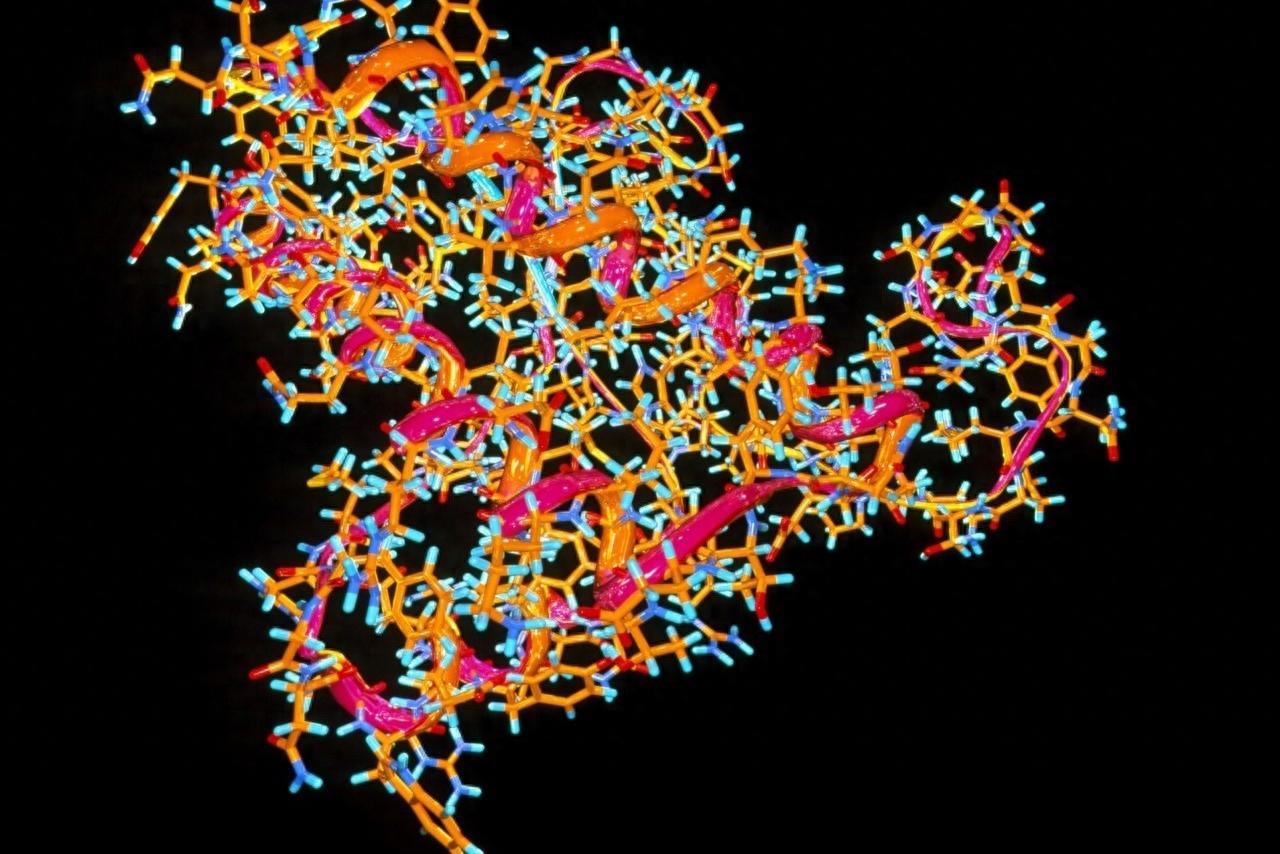

直到1972 年,一位名叫斯坦利·普鲁西纳的教授在看过丹尼尔的报告后,经过仔细研究才确定库鲁病是蛋白质引起的。

并且他天才地认为,朊病毒蛋白平时和正常的大脑上皮细胞蛋白质很像,促成分子完全一样,只是排列顺序不同,于是就比较容易出现基因突变。而且它无法被人类免疫系统察觉到,所以可以潜伏很长时间,后来的研究证实最长可以潜伏50年。

出现基因突变的朊病毒,会通过这种蛋白质合成的方式继续增加,而吃被感染者的大脑显然是更容易积累朊病毒的方式,所以才会出现食人族更容易得库鲁病的现象。